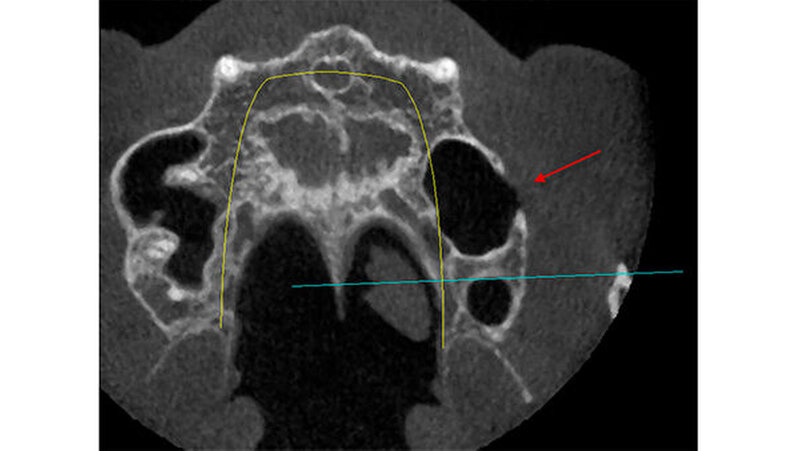

So planten wir für den März 2014 einen Sinuslift mit Augmentation und die Insertion zweier Implantate. Während dieses Eingriffs wurde ein Defekt in der buccalen Sinuswand deutlich sichtbar. Anscheinend bindegewebig war die Schneider`sche Membran durch den Knochendefekt mit der Wangenschleimhaut verbunden (Abbildung 1). Nach Durchtrennung des Gewebes und einer Abdeckung des Durchgangs mit einer resorbierbaren Membran wurde synthetisches Knochenersatzmaterial eingebracht und die Operation wie ursprünglich vorgesehen durchgeführt. Seither ist die Patientin beschwerdefrei.

Die vor der geplanten Implantation gesichtete DVT hatte zunächst keinen knöchernen Defekt ausgewiesen. Erst bei nochmaligem und kompletten "Durchscrollen" aller Aufnahmen wurde der Defekt sichtbar (Abbildungen 2 bis 5).